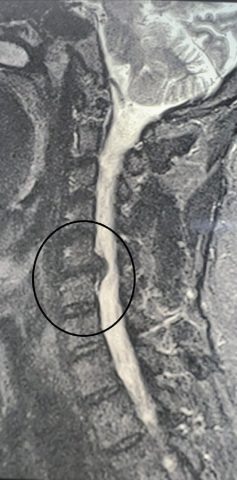

Нейрохирурги спасли воронежца от возможного паралича: они удалили грыжу, из-за которой у мужчины немела рука. Об этом сообщили в группе регионального минздрава во "ВКонтакте" во вторник, 18 ноября. 49-летний мужчина поступил в нейрохирургическое отделение стационара ВГКБ № 11 в конце октября. Пациент жаловался на постоянную боль в шейном отделе позвоночника, онемение и слабость в правой руке. Консервативное лечение не принесло положительного эффекта. Врачи установили диагноз: грыжа диска, спондилоартроз (дегенеративное поражение межпозвонковых суставов, затрагивающее хрящи, костные ткани, связки и околосуставные мышцы), корешковый синдром (радикулит) с чувствительными и двигательными нарушениями. Медики пояснили: если не удалять грыжу, правую руку может парализовать. Нейрохирурги Владимир и Евгений Дроновы удалили межпозвонковый диск и грыжу с использованием операционного оптического прибора, микрохирургической техники и инструментария. Врачи устранили и компрессию спинного мозга и нер

49-летний мужчина поступил в нейрохирургическое отделение стационара ВГКБ № 11 в конце октября. Пациент жаловался на постоянную боль в шейном отделе позвоночника, онемение и слабость в правой руке. Консервативное лечение не принесло положительного эффекта.

Врачи установили диагноз: грыжа диска, спондилоартроз (дегенеративное поражение межпозвонковых суставов, затрагивающее хрящи, костные ткани, связки и околосуставные мышцы), корешковый синдром (радикулит) с чувствительными и двигательными нарушениями.

-2

Медики пояснили: если не удалять грыжу, правую руку может парализовать. Нейрохирурги Владимир и Евгений Дроновы удалили межпозвонковый диск и грыжу с использованием операционного оптического прибора, микрохирургической техники и инструментария. Врачи устранили и компрессию спинного мозга и нервных корешков. Также между двумя соседними позвонками установили межтеловой кейдж – металлическую конструкцию, которая соединила позвонки между собой.